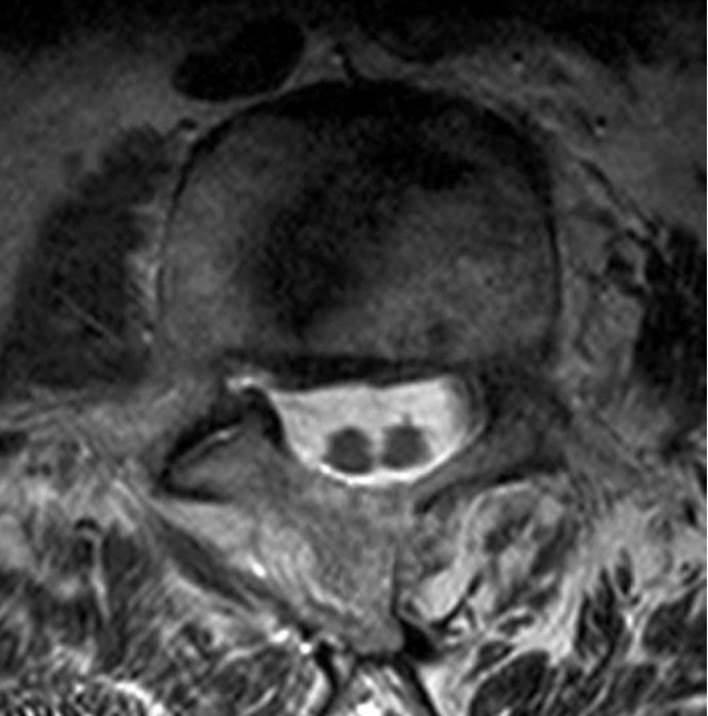

The MRI of lumbar spine shown below shows which abnormality?

Diastematomyelia

Diastematomyelia is a congenital anomaly of the spine characterized by the splitting of the spinal cord or cauda equina at the extent of one or few vertebra. It has been suggested that the cause of this anomaly is the presence of a connection between the neural tube and amniotic cavity or primitive bowel